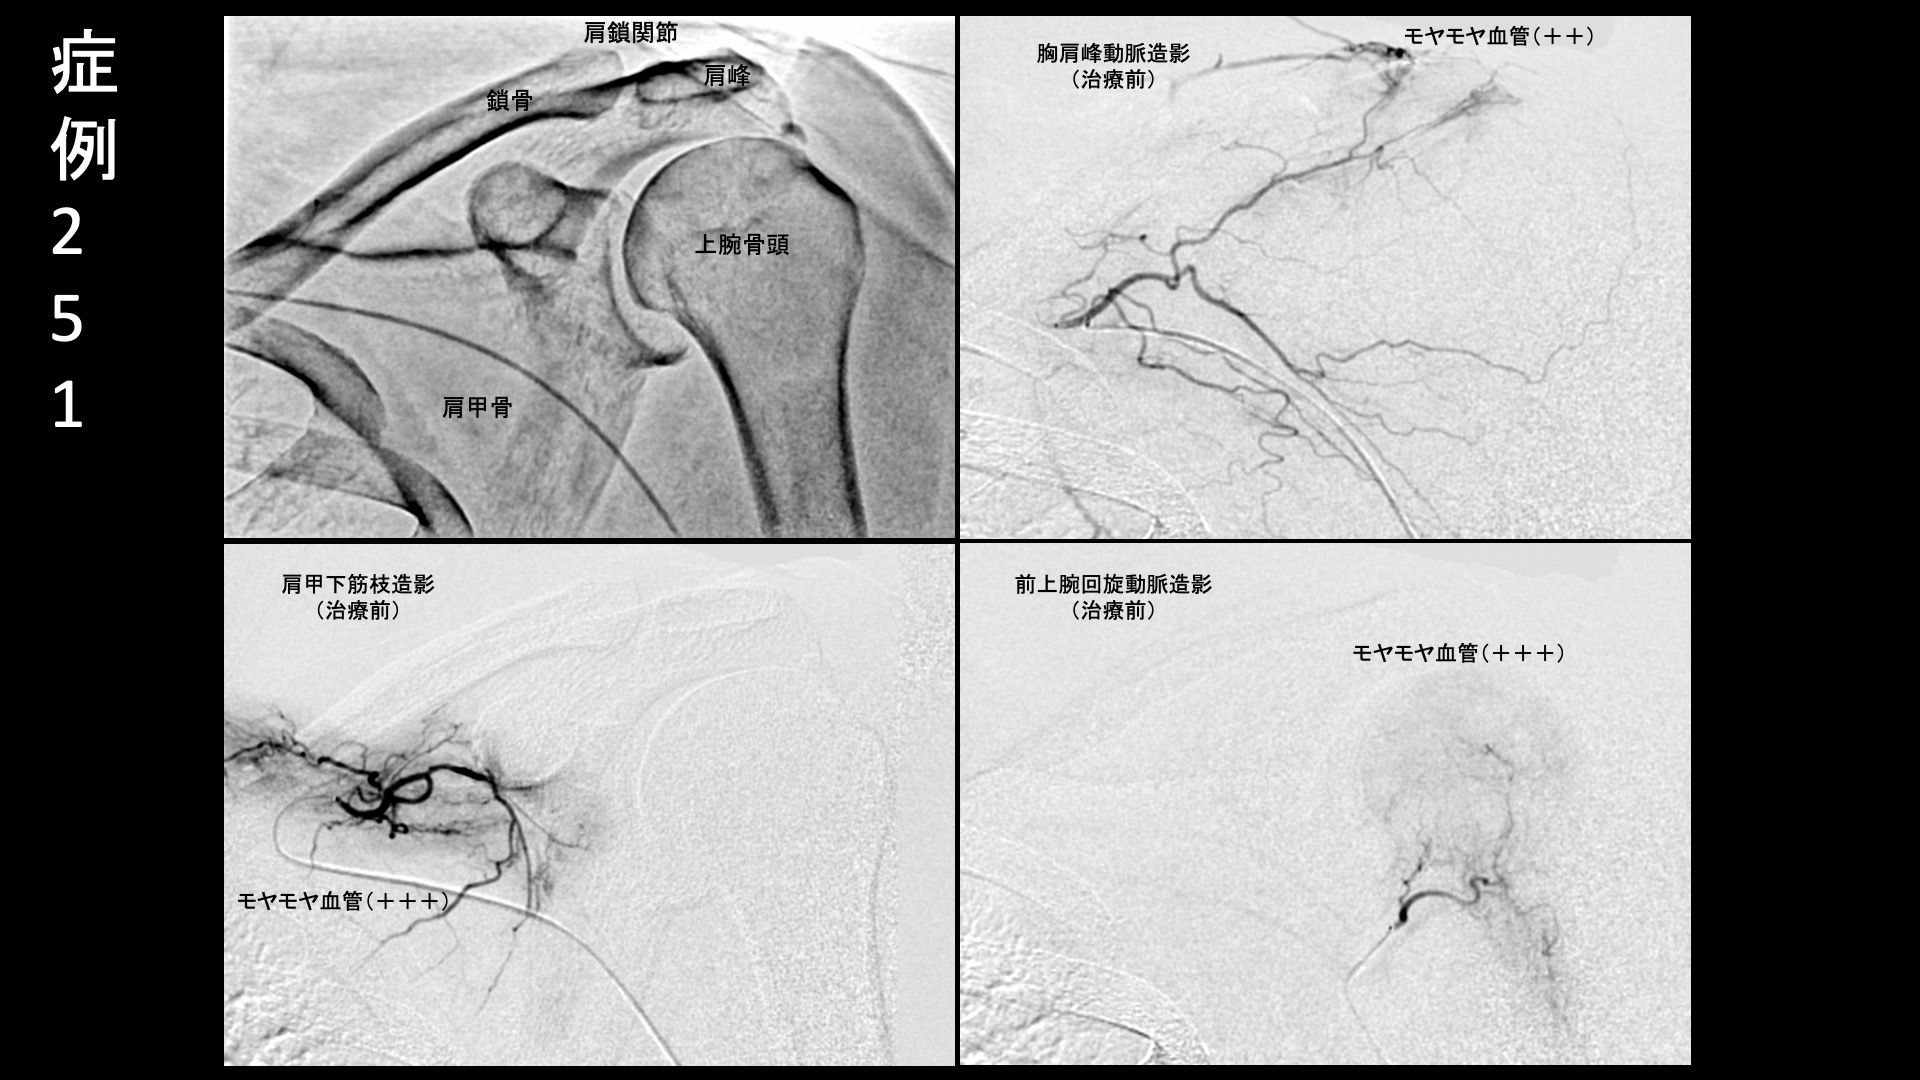

肩:肩こり・四十肩・五十肩 【50代:男性】最初からここに来ればよかった・・ステロイド注射無効で半年間苦しんだ石灰沈着性腱板炎による肩の痛み(石灰沈着性腱板炎、肩関節周囲炎) 2025.11.26 鴨井院長による動画解説 受診までの経過 半年前から左肩が痛むようになり、整骨院や整形外科に通っていました。鎮痛薬内服のほか、ステロイド注射も複数回受けましたが、効果は感じられず、酷くなるばかりでした。腕が挙げられなくなり、ついには夜間痛まで生じるようになりました。当院の治療を知り受診されました。 診察時の所見 腕は水平までも挙がらない状態でした(外転80度)。レントゲンでは腱板領域に石灰を認め、エコー検査では同部位に一致した腱板石灰沈着を認めたほか、周囲に炎症による(モヤモヤ血管を反映した)異常血流信号を認めました。更に、腱板疎部領域や肩鎖関節においても同様に炎症所見を認めました。石灰沈着性腱板炎による肩関節周囲炎の診断です。治療適応と判断し、モヤモヤ血管(病的新生血管)に対する運動器カテーテル治療(微細動脈塞栓術)を受けていただきました。 治療の所見 血管造影を行うと、胸肩峰動脈、前上腕回旋動脈、肩甲下筋枝などでモヤモヤ血管が濃染像として描出されました。特に肩甲上動脈では強い濃染像を認めました。血管造影所見を比べると、石灰沈着性腱板炎では、このように五十肩(凍結肩)よりも強い炎症であることが多いです。ステロイド注射が効かなかったというのも頷けます。いずれも治療後モヤモヤ血管は画像上速やかに消失しました。その他複数箇所の治療を行い終了しました。 治療前画像:損傷を受ける、あるいは繰り返しのストレスにより発生した異常な新生血管 治療後画像:カテーテルを用いて塞栓物質を血管内に投与し新生血管を塞いだ状態 治療費用:治療する部位によって費用が異なりますのでこちらをご参照ください。 主なリスク・副作用等:針を刺した場所が出血により腫れや痛みを生じたり、感染したりすることがあります(穿刺部合併症)。造影剤によるアレルギー(皮膚のかゆみ・赤み・息苦しくなるなどの症状)が出ることがあります。 治療後の経過 治療翌日から改善しました。治療後3週間では、ほとんどの痛みが無くなりました。肩関節の可動域も完全に回復し、バンザイもできるようになりました。半年間苦しんでいた痛みのあまりの回復ぶりに、『最初からここに来ればよかった』と話されるほどでした。エコーで確認すると、まだ石灰沈着については大きな変化はありませんでしたが、今後吸収されていくことも期待できます。非常に経過良好であったことから、終診となりました。石灰沈着性腱板炎は強い炎症を伴っていることが多く、その苦痛も五十肩以上になることが少なくありません。カテーテル治療は強い炎症にこそ、強い効果を発揮します。実際に、本症例では非常に早期から快復しました。罹病期間が長くなければ、石灰も吸収されて無くなります。 非常に良い適応疾患の一つですので、お悩みの方はぜひご検討いただくと良いと思います。 石灰沈着性腱板炎の詳細 【60代:女性】尿が溜まると膣が痛い!夜も寝られず。繰り返す膀胱炎から発症した間質性膀胱炎および膣前庭炎に対するモヤモヤ血管カテーテル治療(間質性膀胱炎、膣前庭炎) 前の記事 【70代:男性】急激に悪化した膝の痛みで歩けなくなり夜も寝られず水も溜まる・・ネフローゼ症候群を合併した変形性膝関節症の実例(変形性膝関節症、ネフローゼ症候群) 次の記事